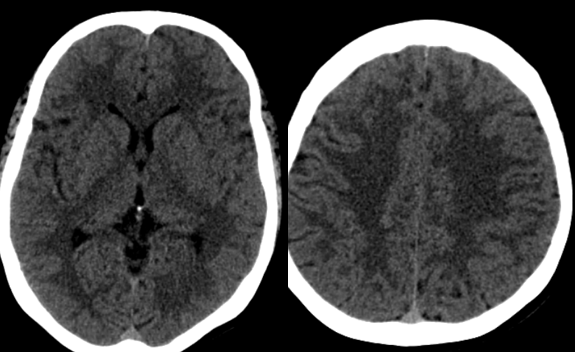

Bệnh nhân được chụp CLVT sọ não không tiêm thuốc: chưa phát hiện bất thường

Bệnh nhân tiếp tục được được chụp CLVT mạch máu não: Phát hiện hẹp khít động mạch cảnh trong trái đoạn mấu giường và động mạch não giữa đoạn M1 hai bên.

Một bệnh nhân trẻ tuổi, CLVT mạch máu não nghĩ nhiều đến hình ảnh của bệnh Moya Moya, vì vậy bệnh nhân được chỉ định chụp DSA mạch não để khẳng định chẩn đoán đồng thời tiên lượng khả năng điều trị bệnh.